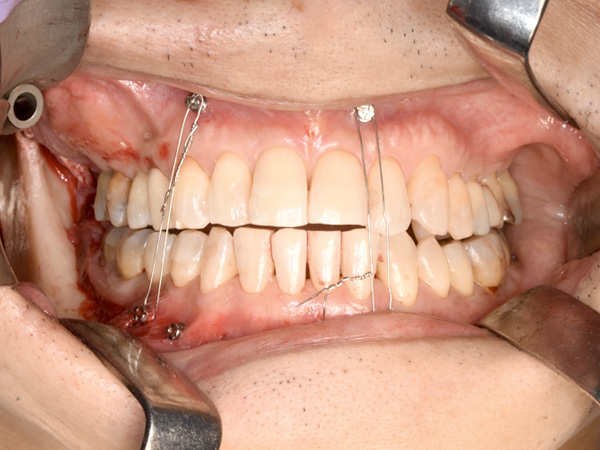

ワイヤーで上下を縛り、嚙み合わせを確認します。

確認したら、ワイヤーはその場で外します。